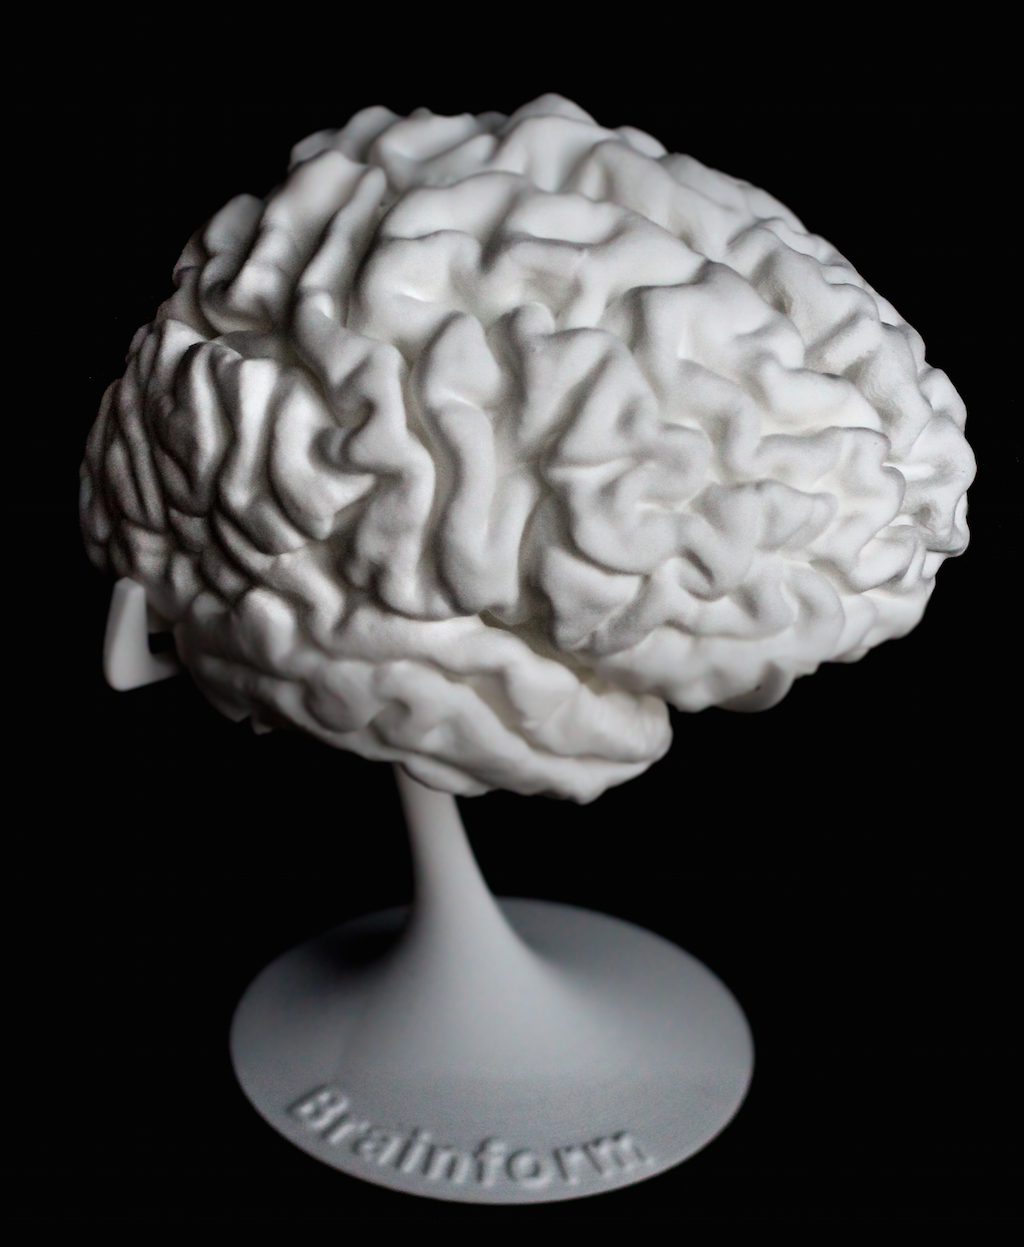

It’s now possible to obtain a 3D printed model of your own brain.

Brainform is a specialized 3D print service that uses MRI scan data to create detailed prints of human brains. While printing a 3D model is pretty straightforward these days, obtaining MRI data might not be.

The prints are literally a “brain on a stem” and appear suitable for educational and personal use. A custom, life-size personal brain print printed on an SLS 3D printer is priced at USD$340, whereas a half-size brain print is priced at USD$110. Stock brain prints are a bit less.

It may seem like a natural progression of technology to see the arrival of a 3D print service that can use MRI scan data to produce a 3D model of your brain, but that’s where we are today. You can actually press a button and receive a print of your brain.